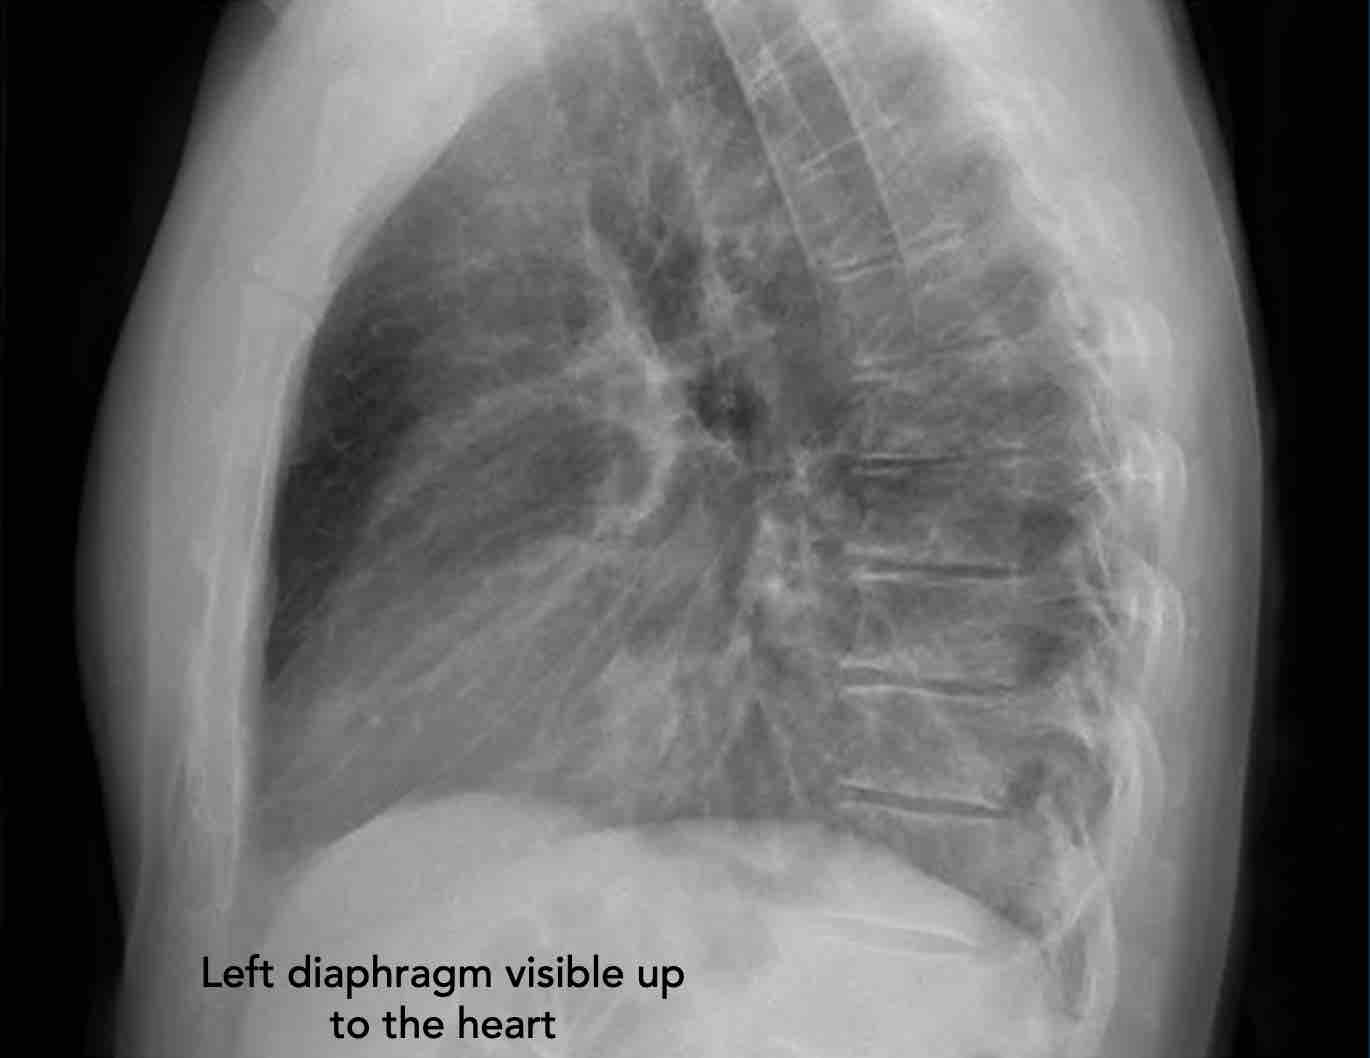

- Vòm hoành phải phải được nhìn thấy rõ ràng ở phía trước đến tận thành ngực (mũi tên đỏ), thể hiện ranh giới giữa phổi có khí và mô mềm ổ bụng.

- Vòm hoành trái thường chỉ nhìn thấy đến điểm tiếp giáp với bóng tim (mũi tên xanh lam), phía ngoài điểm đó ranh giới bị mất do tỷ trọng tương đương giữa tim và các tạng bụng phía trên.